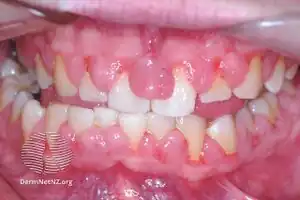

| Gingivitis, a common cause of inflammatory gingival enlargement. | |

Gingival enlargement has a multitude of causes. The most common is chronic inflammatory gingival enlargement, when the gingivae are soft and discolored. This is caused by tissue edema and infective cellular infiltration caused by prolonged exposure to bacterial plaque, and is treated with conventional periodontal treatment, such as scaling and root planing.[1]

The accumulation and retention of plaque is the chief cause of inflammatory gingival enlargement. Risk factors include poor oral hygiene,[5] as well as physical irritation of the gingiva by improper restorative and orthodontic appliances.[1]